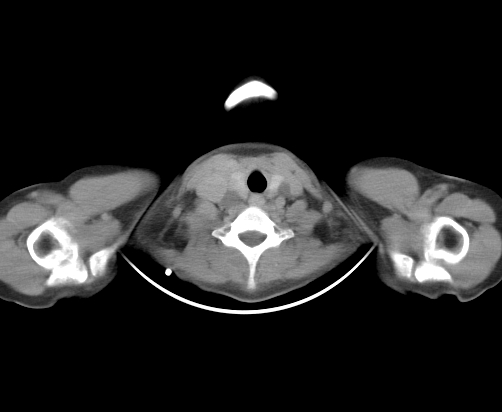

胸部